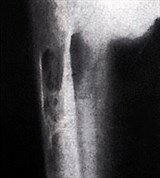

Усиленная секреция паратгормона способствует повышенному выходу кальция и фосфора из костей в кровь. В результате костная ткань перестраивается, размягчается, кости искривляются, становятся ломкими. Паратгормон, воздействуя на почки, может способствовать усиленному выходу фосфора с мочой. Это компенсируется еще большим исходом фосфора из костной ткани. В то же время, повышенное содержание кальция в крови снижает нервно-мышечную возбудимость и способствует снижению тонуса мышц. Кроме того, избыток кальция предрасполагает к образованию камней в почках, что приводит к развитию тяжелой почечной патологии.

Диагноз ставится на основании следующих симптомов: слабость, боли в животе и костях, язва желудка, камни в почках, высокий кальций в крови, костные изменения на рентгеновских снимках.